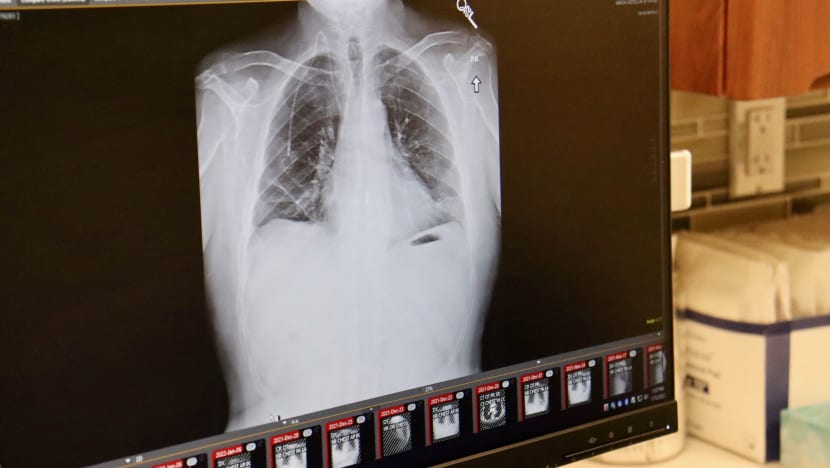

(Gambar: Northwestern Medicine/AFP)

Justeru, dia dibekalkan dengan pelitup oksigen dengan segera dan doktor pun melakukan X-ray.

Hasil keputusannya menunjukkan bahawa paru-paru pesakit berkenaan dipenuhi dengan cecair. Oleh itu, paru-parunya harus ditebuk supaya cecair itu dapat dikeluarkan.